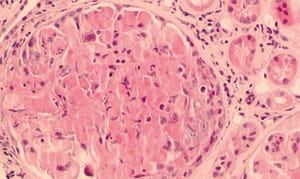

El compromiso más característico es una glomerulonefritis necrotizante focal segmentaria acompañada con proliferación extracapilar con componente pauciinmune y formación de media lunas, se puede manifestar entonces como una glomerulonefritis rápidamente progresiva, no hay depósitos de inmunoglobulinas o complemento en la inmunofluorescencia. Estas manifestaciones se han descrito en 80 % casos y es una de las manifestaciones más importantes y graves de la enfermedad.14